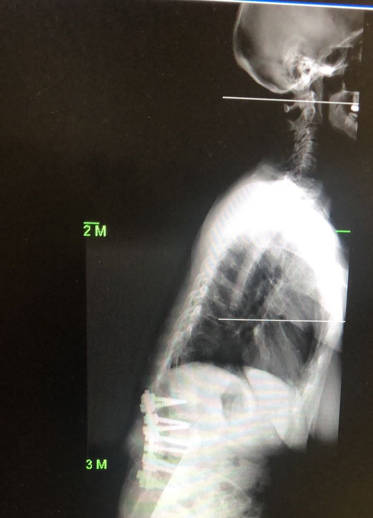

En el post, el equilibrio de la espalda, hablábamos de la importancia de mantener una postura equilibrada en la que el peso de la cabeza recaiga sobre la pelvis. Con la edad aumentaba la rigidez y se perdían las curvas de la espalda por lo que teníamos tendencia a inclinarnos hacia delante. En esta situación existen mecanismos de compensación, consistentes en levantar la cabeza, adelantar la pelvis o flexionar las rodillas. Por lo tanto en la enfermedad de Párkinson se da el coctel perfecto para tener una columna mal equilibrada, dificultad para mantenerse erguido debido a la debilidad muscular y una ausencia de mecanismos de compensación debido a la rigidez, sin olvidar una calidad de hueso peor debido a la osteoporosis.

Por desgracia, mantener el equilibrio sagital es fundamental para conseguir buenos resultados quirúrgicos y en los pacientes con Párkinson es más difícil de conseguir.

En los casos más avanzados en los que ya tengamos una deformidad (escoliosis o cifosis) la cirugía se convierte en un auténtico reto para el cirujano. Hay que restablecer el equilibrio sagital lo cual es técnicamente complejo, además los pacientes con Párkinson tienen un margen de error menor que el resto de los pacientes. Y aunque recuperemos el equilibrio sagital y la cirugía técnicamente sea un éxito, el propio avance de la enfermedad va a provocar la reaparición del desequilibrio y por lo tanto las condiciones para que la cirugía fracase. En estos caso quizás la mejor decisión sea la abstención y no indicar cirugía en estos pacientes ya que las complicaciones y las reintervenciones están prácticamente garantizadas.